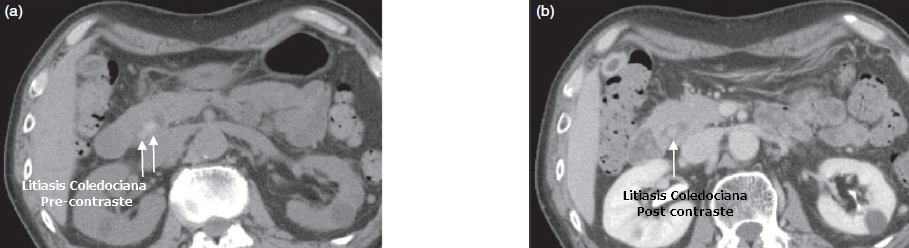

Hallazgos Tomográficos